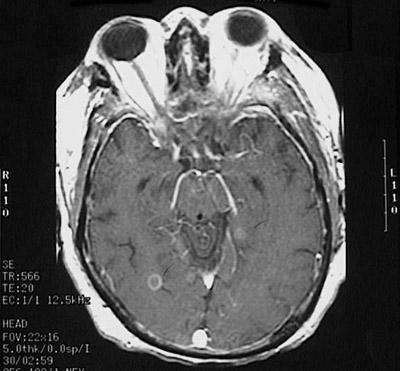

Click on the cerebral abscess in the MRI scan above:

This magnetic resonance imaging (MRI) scan of the head in transverse (axial) view demonstrates a small enhancing abscess in the posterior parietal region of the brain in a patient who had septicemia.